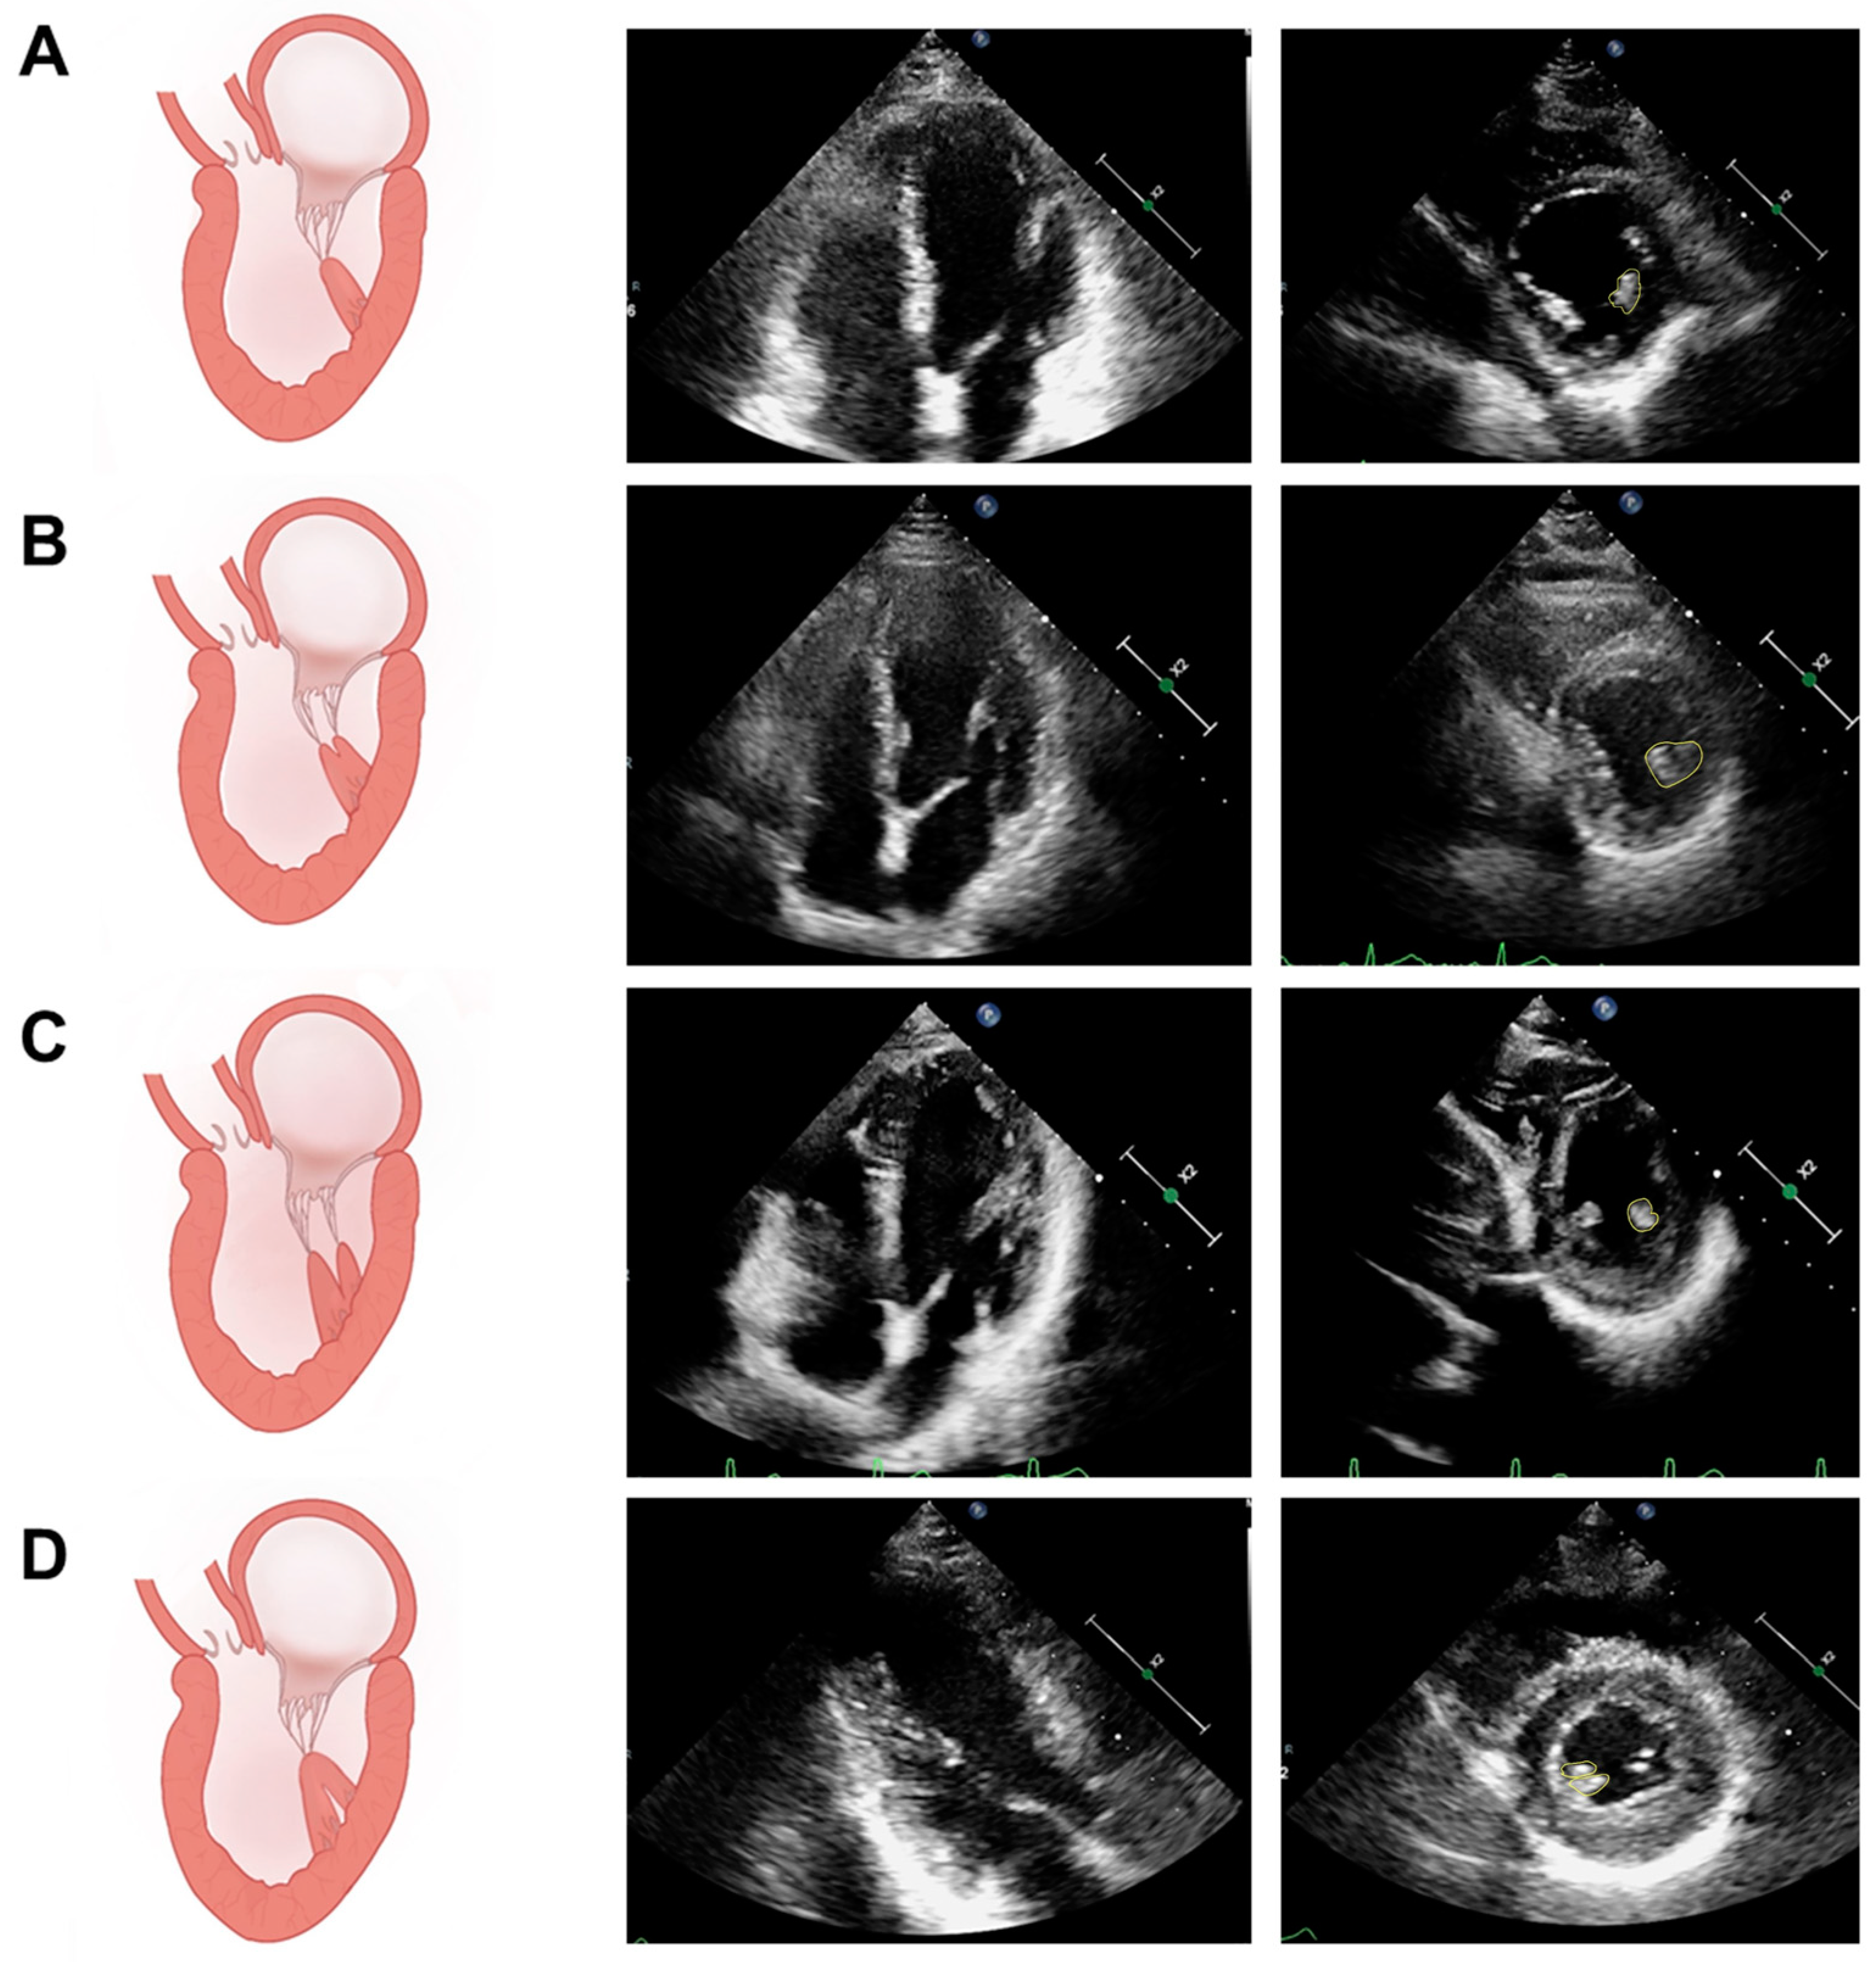

5.1. Assessment of PM Structure

5.2.1. Qualitative Assessment of PM Function